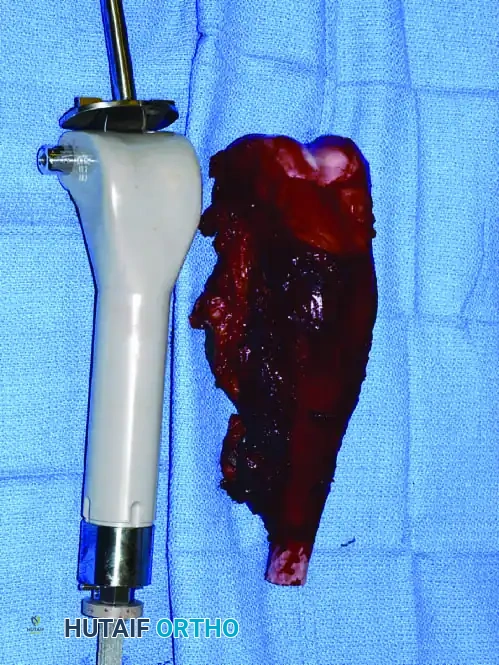

* Osteotomize the humerus at the preoperatively determined level and remove the specimen en bloc. Confirm adequate margins via frozen section analysis.

Intraoperative Imaging and Margin Assessment

Continuous intraoperative assessment using fluoroscopy and frozen section pathology is mandatory. The following images demonstrate various stages of complex upper extremity resections, allograft preparations, and prosthetic implantations across the humerus and elbow joint.

Distal Humerus and Elbow Reconstruction

When tumors involve the distal humerus, resection often requires sacrifice of the collateral ligaments and the articular surface of the elbow. Reconstruction is typically achieved using a linked, semi-constrained total elbow arthroplasty designed for oncologic defects.